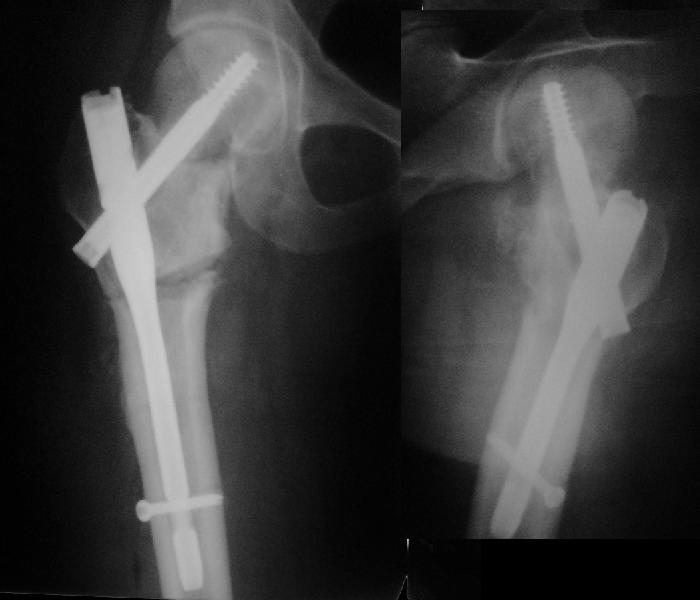

В итоге что-то такое и сделали. Убрали DHS, остеотомия, синтезировали Affixus с небольшой вальгизацией. Снимки в приложении.